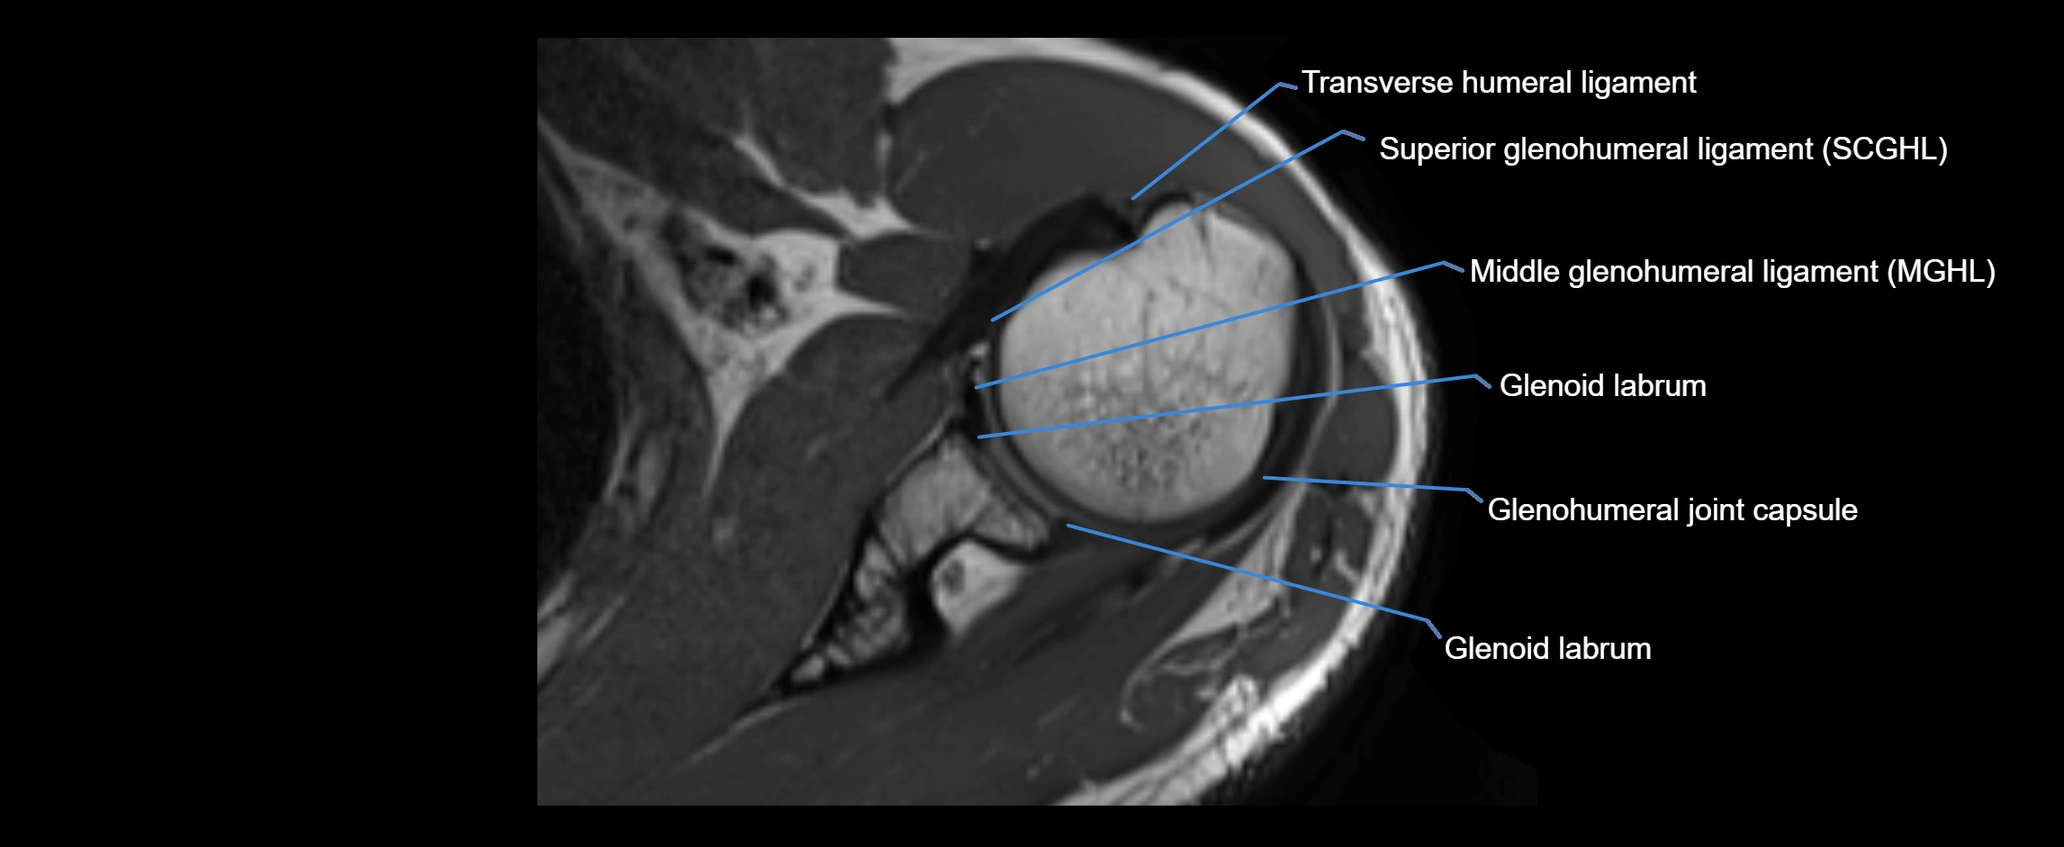

MRI Appearance

• T1-weighted images:

• Normal ligament: Low signal (dark linear band) spanning acromion to clavicle.

• Surrounding fat planes: Bright, delineating the ligament clearly.

• Marrow of clavicle and acromion: Bright due to fatty content.

• Tears: Discontinuity or irregular thickening with intermediate-to-bright signal.

• Chronic injury: Thinning, fraying, or irregular low-signal fibers with adjacent scarring.

• T2-weighted images:

• Normal ligament: Low signal, homogeneous.

• Partial tear or sprain: Focal hyperintensity or thickening.

• Complete tear: Discontinuity with fluid-bright gap between clavicle and acromion.

• Associated edema: Bright signal in distal clavicle or acromion marrow.

• STIR:

• Normal ligament: Dark linear band.

• Injury or inflammation: Bright hyperintense signal in and around ligament fibers.

• Highlights periligamentous soft-tissue edema, especially in acute trauma.

• Proton Density Fat-Saturated (PD FS):

• Normal ligament: Low signal, uniform thickness.

• Partial tear or sprain: Bright signal or contour irregularity.

• Complete tear: Clear discontinuity with bright signal gap and joint effusion.

• Excellent for assessing joint capsule, coracoclavicular ligaments, and periarticular edema.

MRI images

image